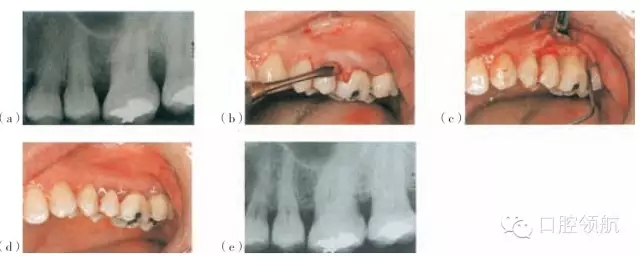

圖26.5 使用Emdogain®和PerioGlas®處理的一個病例。(a)手術(shù)位點(diǎn)的術(shù)前放射線圖像。(b)頰側(cè)瓣的影像。(c)使用EDTA調(diào)節(jié)器后應(yīng)用Emdogain®。(d)瓣的復(fù)位與縫合。(e)術(shù)后18個月的放射線圖像

Straumann®, Emdogain也可以被用在骨移植材料的結(jié)合處,例如作為骨沉積的支架(圖26.5)的Bio-Oss®(GeistlichPharma AG),PerioGlas®或者StraumannBoneCeramic 400-700®。Emdogain®還可以與GTR技術(shù)聯(lián)合應(yīng)用。